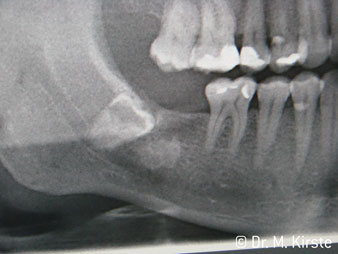

45° açılı angldruva geniş avantaj yelpazesi sebebiyle özellikle seçildi. Bu enstrümanın geliştirilme nedeni olan cerrah meslektaşlarım angldruvaların kısıtlı alanlardaki çalışma yeteneğini yakında takdir edeceklerdir. Özellikle gömük diş çekimlerinde (res. 2) yumuşak dokunun yanak bölgesine doğru yarılmasına gerek kalmaz(res. 3). Angldruvanın kafa dizaynı sayesinde retromolar bölgede hızlı ve güvenli çalışma sağlar.